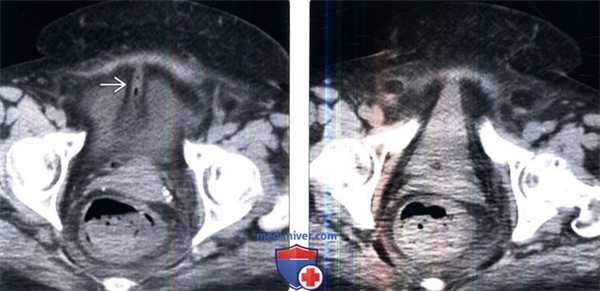

(Слева) КТ с контрастированием, аксиальный срез: диастаз лобкового симфиза и скопление жидкости в мягких тканях спереди; зачастую затруднительно определить, является ли это скопление мочой или гематомой, или и тем, и другим.

(Справа) Контрольная цистография, передняя проекция: у этого же пациента определяется экстравазация контраста из мочевого пузыря в ткани внебрюшинного пространства, окружающие мочевой пузырь, а также вдоль верхней трети левого берда и мошонки. Небольшое количество контраста определяется в мочевом пузыре. (Слева) КТ с контрастированием, выполненная для оценки первичной травмы, аксиальный срез: околопузырное скопление жидкости. Дифференциальный диагноз включает скопление мочи или крови. Небольшое кровотечение заметно в подкожной клетчатке спереди и в околопрямокишечном пространстве.

(Справа) КТ-цистография, аксиальный срез: у того же пациента выявлено, что околопузырное скопление жидкости является экстравазатом контрастируемой мочи, вследствие внебрюшинного разрыва мочевого пузыря. Обратите внимание на внебрюшинное скопление контраста в околопузырных пространствах, которое имеет форму моляра.